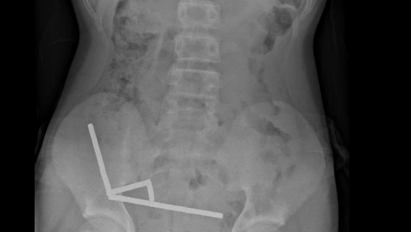

Raio-x abdominal do menino que engoliu entre 80 e 100 ímãs de alta potência (Foto: New Zealand Medical Journal).

Exames revelaram que os ímãs haviam se agrupado em quatro correntes na parte inferior direita do abdômen, unindo diferentes seções do intestino com sua força magnética. A atração dos ímãs era tão forte que chegou a distorcer algumas das imagens dos exames.